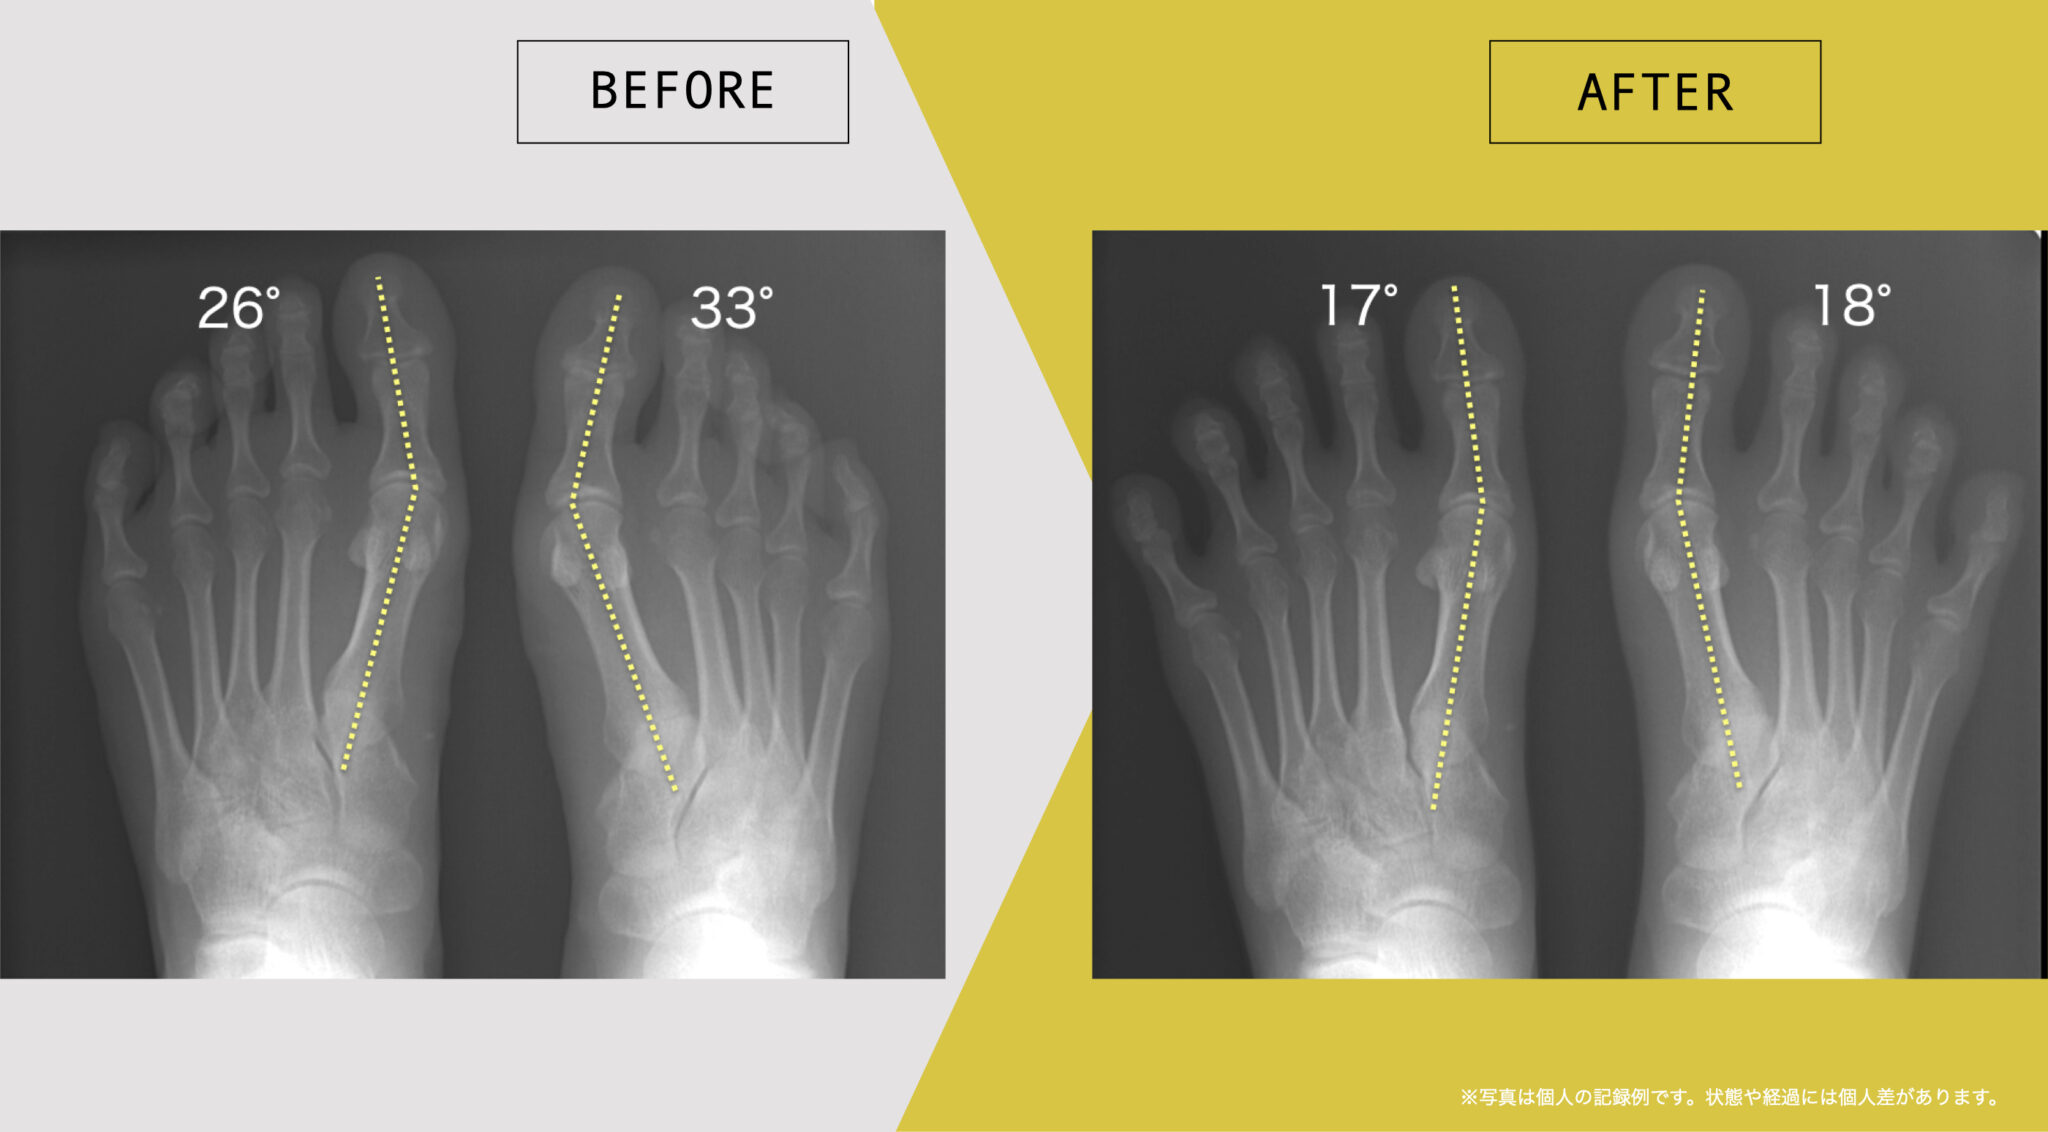

足指や姿勢の状態に関する記録例

ここでは、日常生活の中で足指のセルフケアを継続された方について、足指や姿勢の状態を記録した一例をご紹介します。

これらは、医療的な効果や症状の改善を示すものではなく、生活習慣の中での足指の状態を個別に記録した参考例です。同様の結果が得られることを示すものではなく、状態や経過には個人差があります。